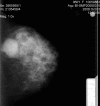

A patient without clinical symptoms had a mammogram in October 2008. The procedure caused intense persistent pain, swelling and development of a haematoma following mediolateral left breast compression. Three months later, a 9×11 cm mass developed within the same region. Core biopsies showed a necrotizing high-grade ductal carcinoma, with a high mitotic index. Owing to its extensive size, the patient began chemotherapy followed by trastuzumab and later radiotherapy to obtain clear margins for a subsequent mastectomy. The mastectomy in October 2009 revealed an inflammatory carcinoma, with 2 of 3 nodes infiltrated by the tumour. The stage IIIC tumour, oestrogen and progesterone receptor negative, was highly HER2 positive. A recurrence led to further chemotherapy in February 2011. In July 2011, another recurrence was removed from the mastectomy scar. She died of progressive disease in 2012. In this article, we discuss the potential influence of compression on the natural history of the tumour.